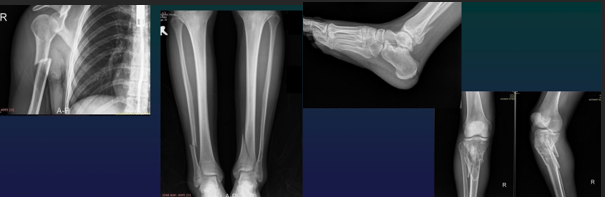

MSK Trauma Rof of Imaging

Positive Dg + lesion type

Monitoring + Dg complications

METHODS

CT (complex fractures)

Conventional Xray

Septic Arthritis Rx

Normal Rx

Intraarticular effusion

Periarticular OP

Joint space narrowing

Blurred cortical bone

Subcondral bone destruction

Erosion + osteomyelitis

Ankylosis (rare)

Septic Arthritis

Agent: Staph

Seeding: hematoG, direct and contiguity

Predispo F:

local: RA, arthrosis, trauma, microcristal arthritis, neurotropathy

general: hémopathies, DM, cancer, chronic renal failure, immune deficit, drug abuse

Loc: any joints

more fq= hip (kids), knee (adults) and SI or sternoclavicular in DM, HIV and drug abuse

Osteomyelitis (nelaton in 1844)

Agent: Staph Aureus (75%) or streptococci & other germs

Contamination

Hematogenous

Contiguity

Direct seeding: accidental & iatrogenous

Affecting: any age, more fq in children M/F=3/1

Slow emergence

at 24-48h: increased soft tissue opacity and thinning if adipose tisse

at 7-10 d: OP, foci of Osteolysis and thinning blade shaped periostosis (3-6 wks)